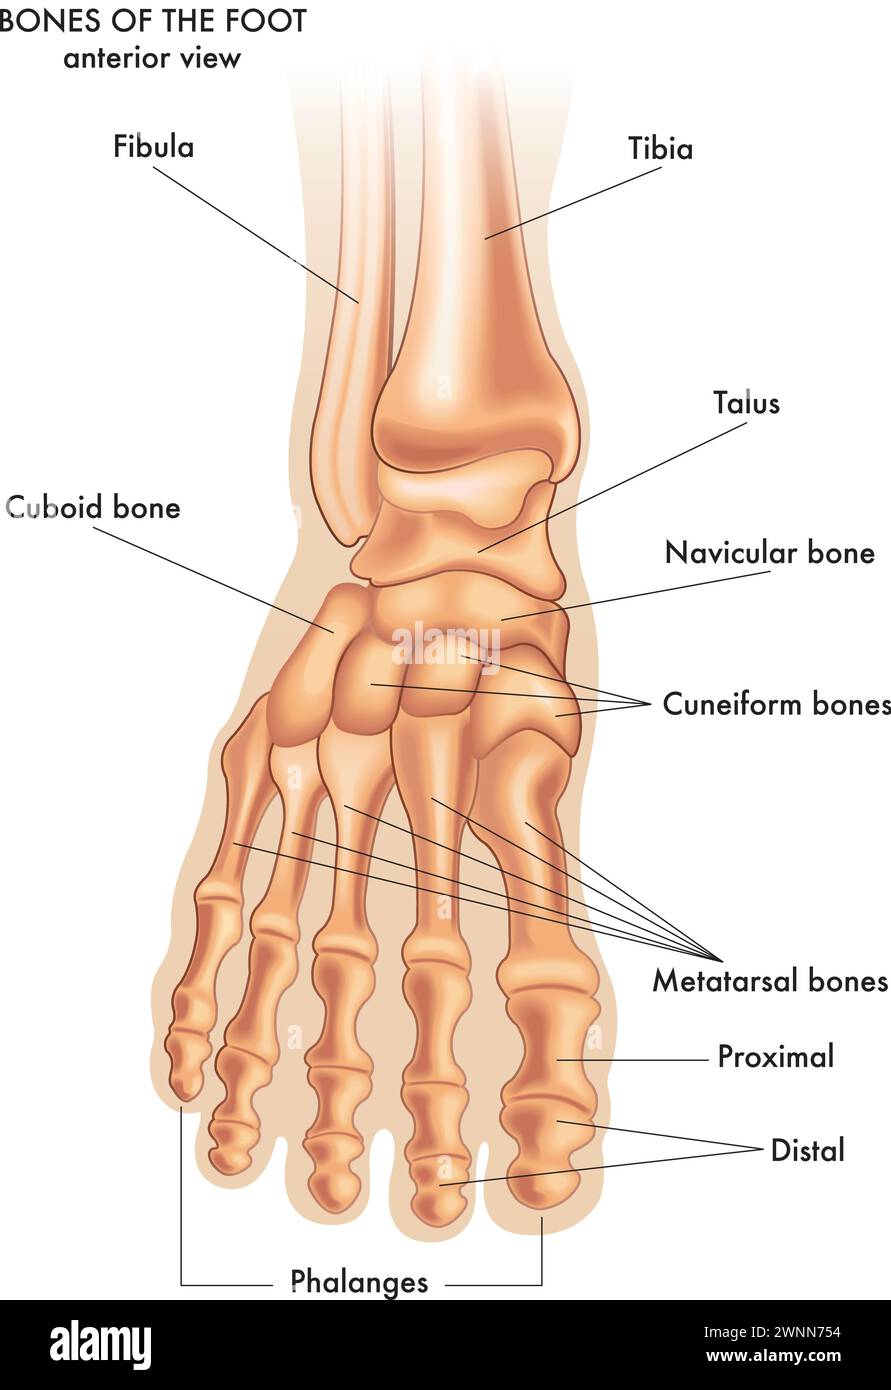

RF2WNN754–Illustration médicale des principales parties des os du pied en vue antérieure, avec annotations.